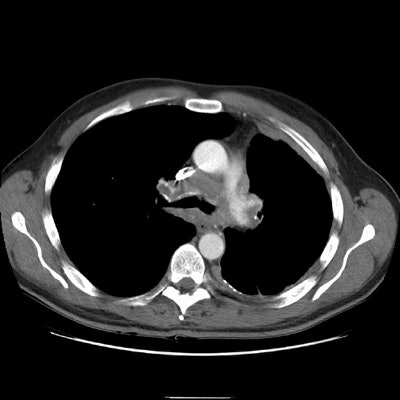

The right upper lobe pulmonary vein can be seen just lateral and slightly posterior to the SVC. It is markedly narrowed and distorted by the mediastinal infiltrative soft tissue abnormality. No left upper lobe pulmonary vein is identified. The left pulmonary artery structures are narrowed and irregular.

Again note abnormality involving the left pulmonary artery and airway narrowing.